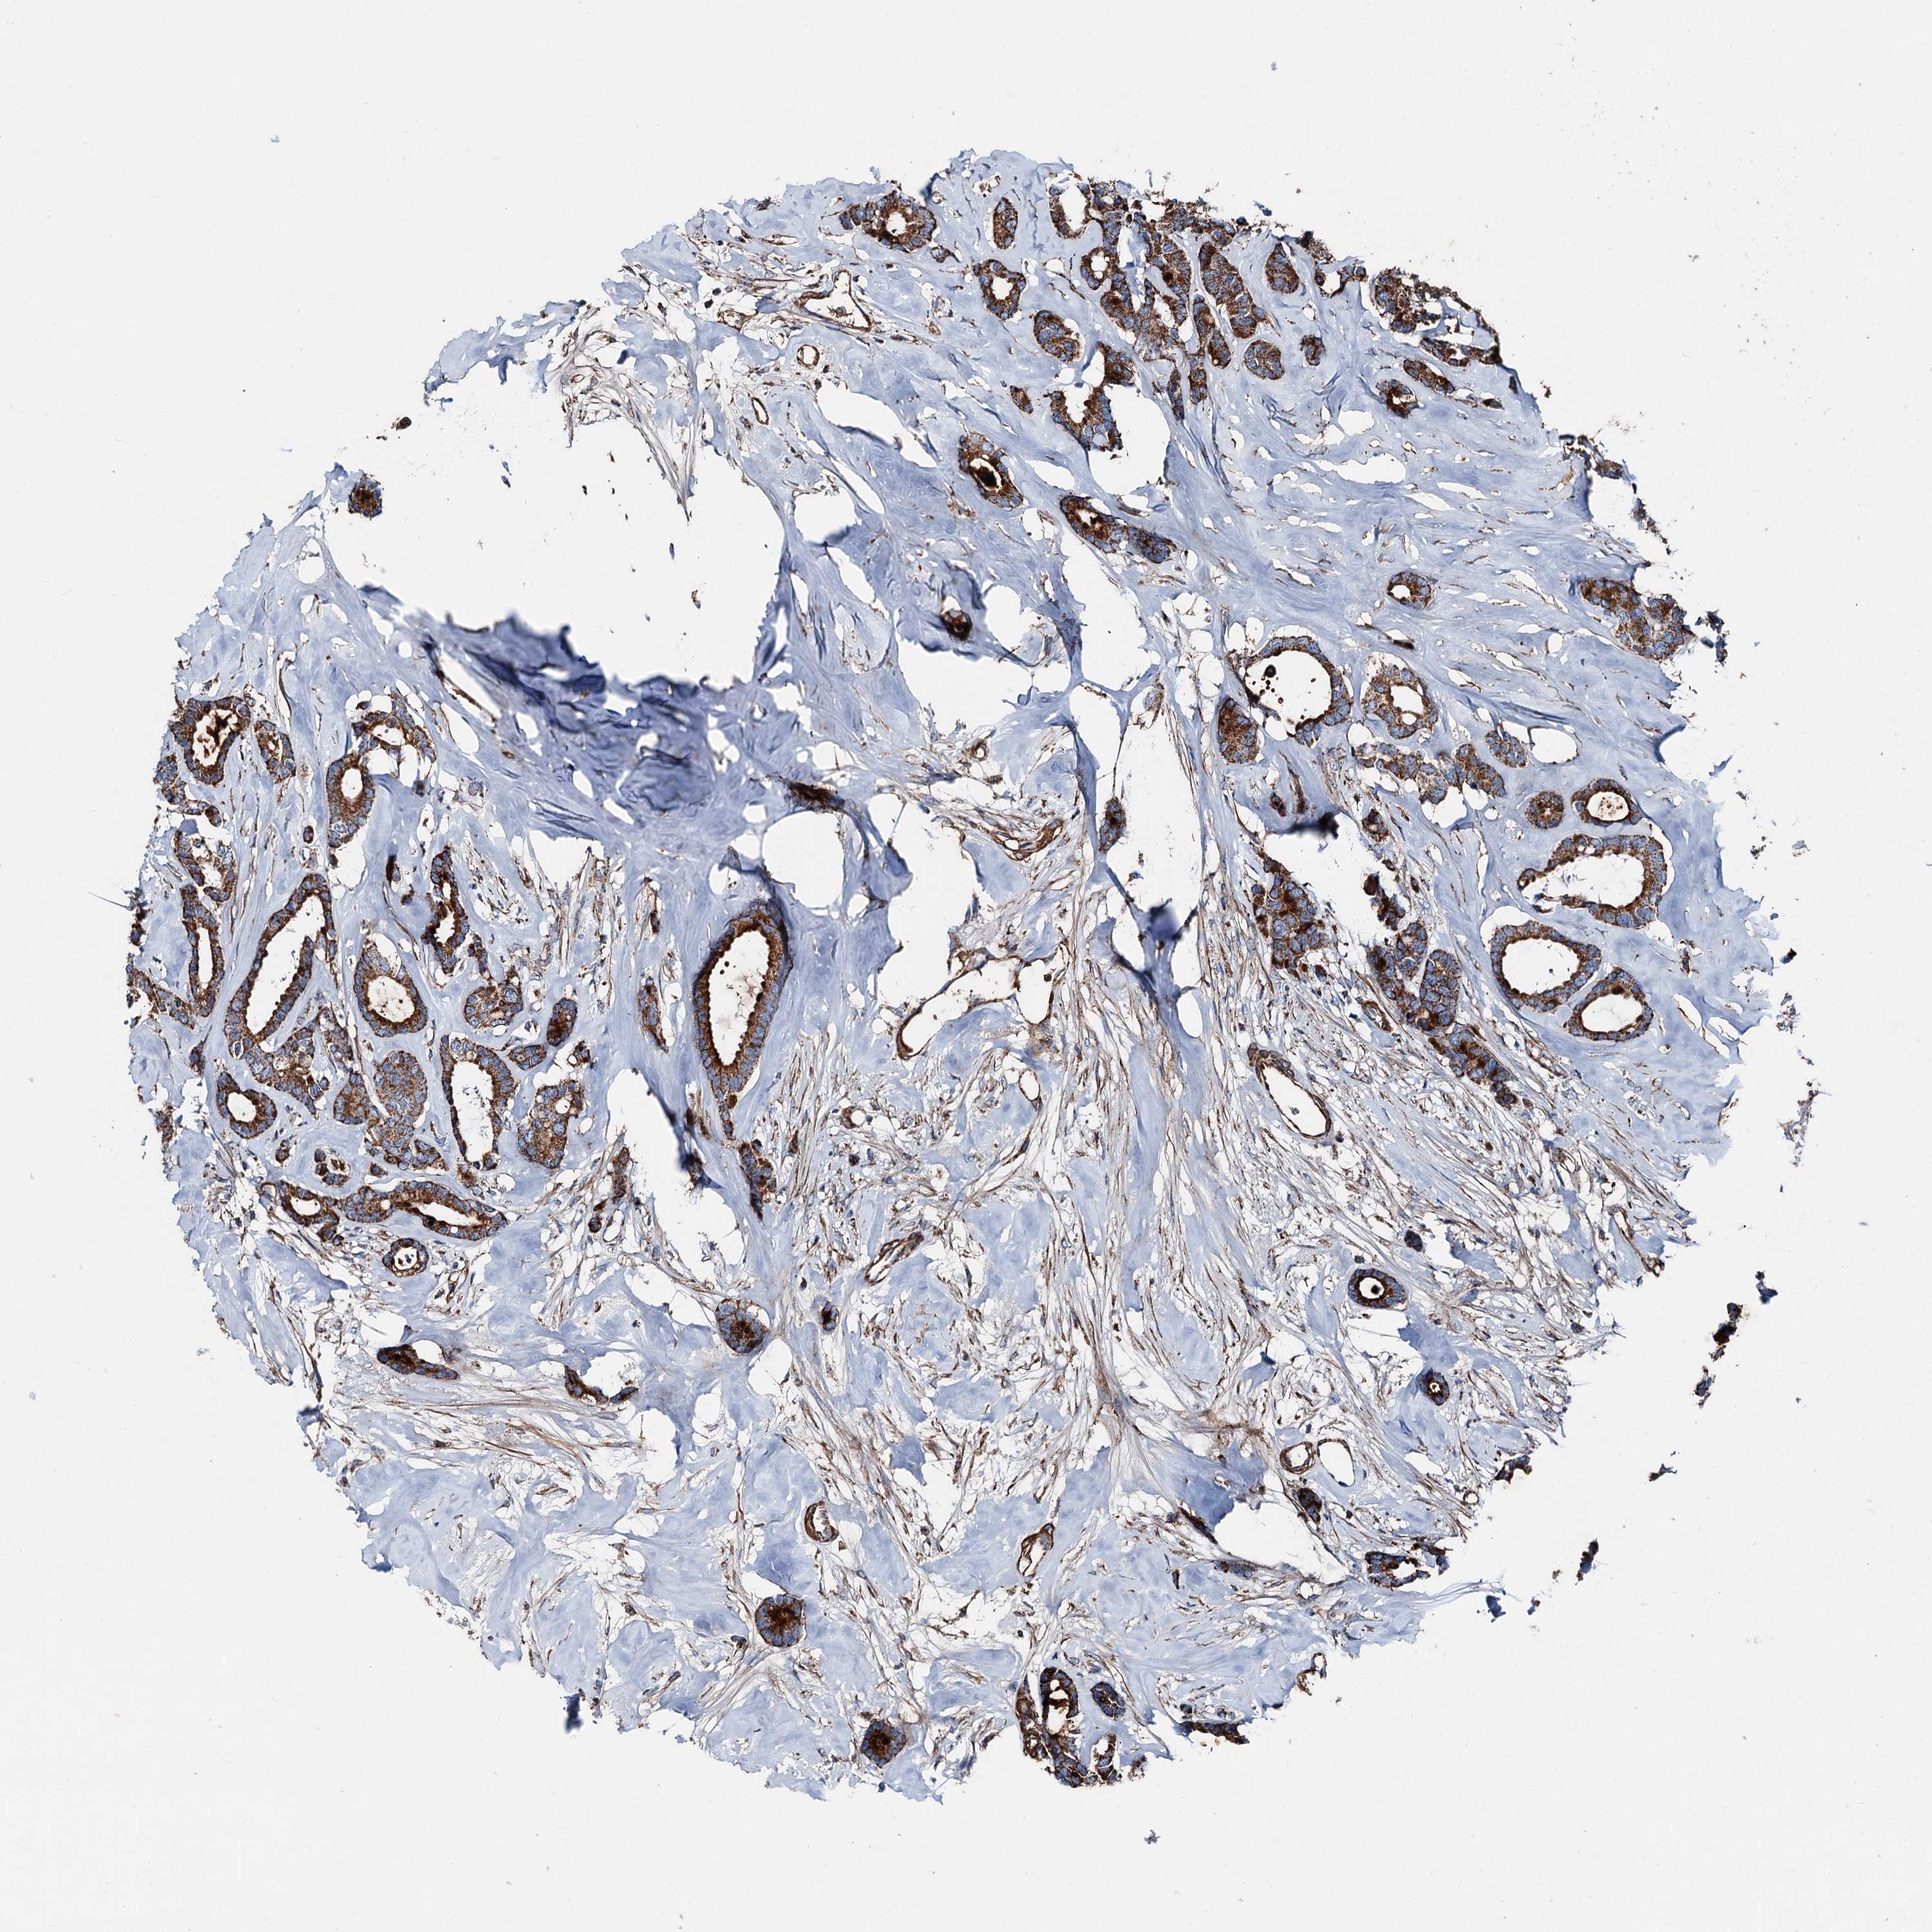

BRCA TCGA BRCA VALIDATION PROTEIN EXPRESSION